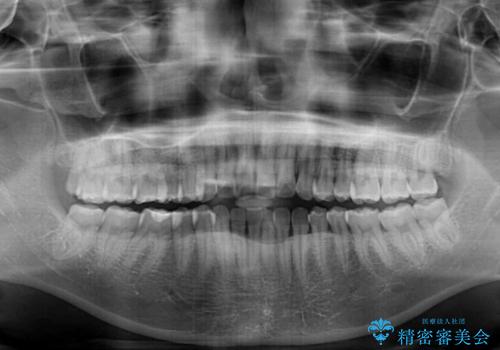

- 前歯のデコボコと上下前歯の隙間を気にして来院された患者様です。

下顎前歯はデコボコのため、歯肉が腫れやすくなっていました。

また、舌突出癖のため、上下前歯の間に隙間ができてしまい、上顎前歯が前方に傾斜している状態でした。

舌突出癖改善のためのトレーニングを行いながら、インビザラインにて矯正治療を行うこととしました。